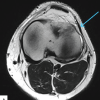

It was tender to touch, and terminal extension was restricted due to pain. Radiographs of the bilateral knee revealed a bipartite patella, Saupe type three variant (Superolateral) [2]. Further, magnetic resonance imaging was done to rule out associated meniscligamentous pathologies (Fig. 2 and 3).